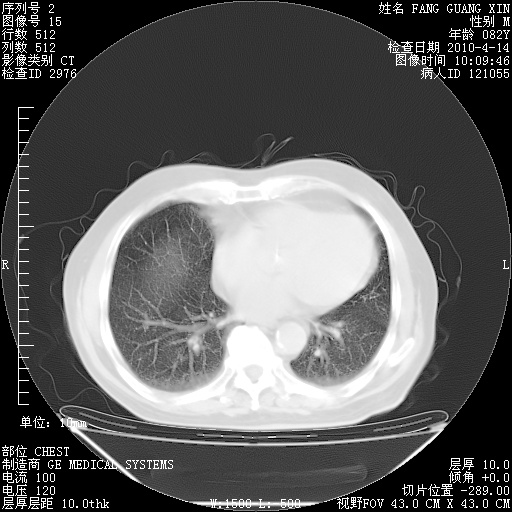

4月14日肺部CT